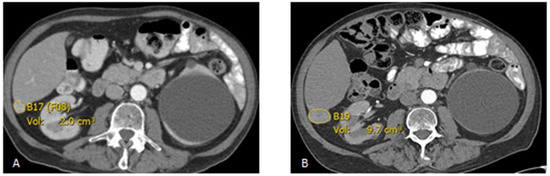

2.2. Imaging Analysis